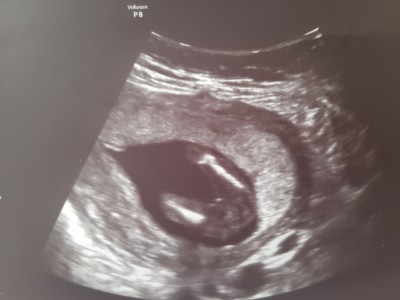

imageikiside aynı gün alınmış resimler kizlar

Gebelik haftası 16

Hiç anlamam ama bacak arası boş değil doktor ne dedi ben erkeğe benzettim

Kıza benzetti ama bende bacak arasi dolu diye görüyorum

Erkeğe benziyor ama ilk resimde boş arası ikinci resim yanıltıyor olabilir ilk resimi baz alırsak kız gibi

Kız. Bizimkinin bacak arası kocaman elma gibiydi. Erkek çok daha belirgin oluyor.

Bacak arası boş yani o bebek vajeni biraz dışa cıkık durur. Erkek olsa daha fazla doluluk olurdu. Gerçi ayına göre testisler Yukarda oluyor erkekler dede. Doğduktan sonra yada doğuma yakın da inebiliyor. Yani tam karar veremedim ama popo çıkıntısı yani arka kemik erkeklerde daha dışa dönük kızlarda daha tombul duruyor.

Şükür birisi cinsiywt için bacak arası resmi attı.bu resimde bacak arası boş kız olma ihtimali yüksek geldi bana ama doktorun tekrar bakmalı ki kesin bilgi olsun